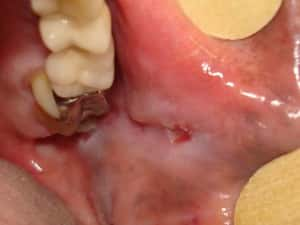

Úlcera Traumática em mucosa jugal